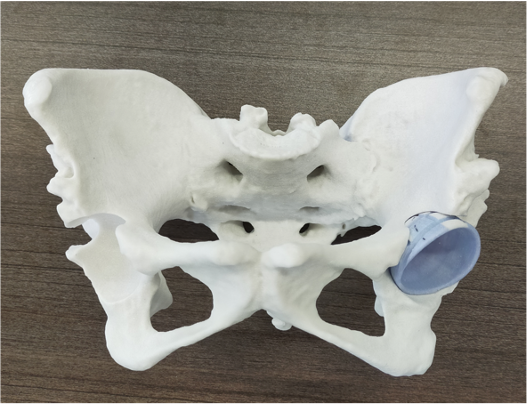

CT画像データをもとに作成した股関節(大腿骨頭)の骨モデル。

実物とまったく同じ大きさ、同じカタチで、細かい骨のデコボコまで正確に再現されています。

この三角形のがオーダーメイドの患者適合型ガイドです。

手術時に実際の骨に乗せて固定し、ガイドに沿って骨を切除すると、術前計画通りの骨切りを正確に再現することができます。

骨盤側(臼蓋)の骨モデルです。インプラントが設置された状態になっていて、骨とインプラントの位置関係を把握することができます。